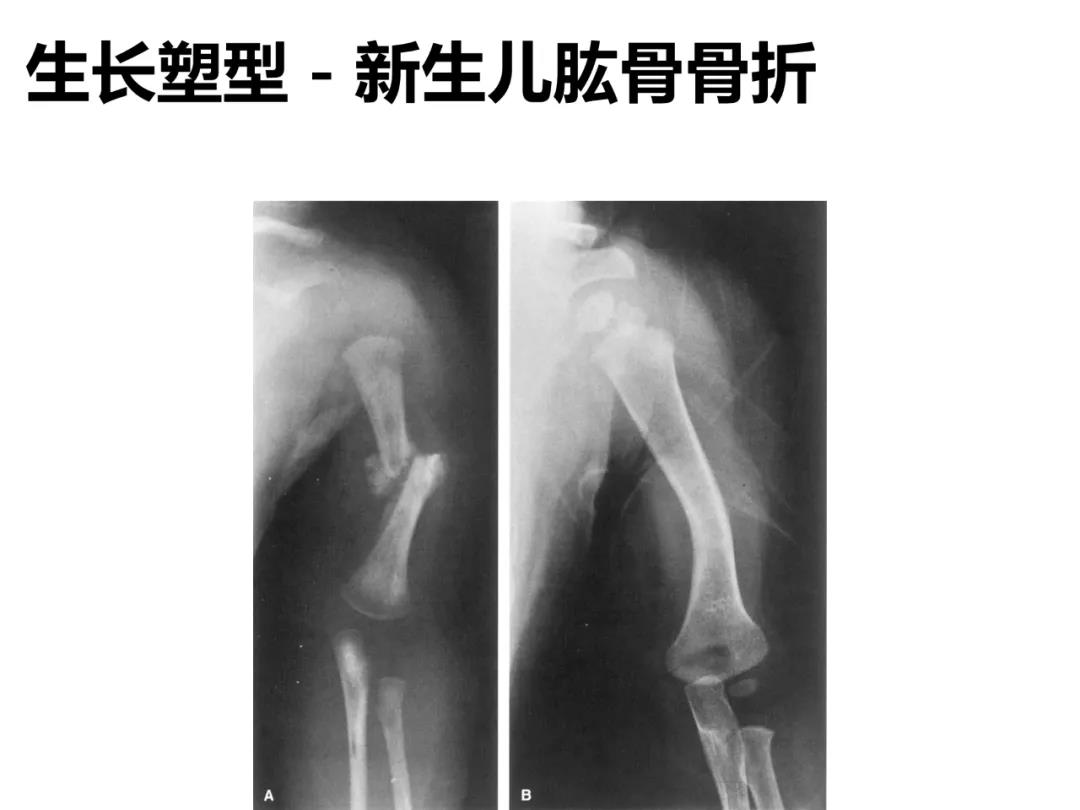

小儿骨科X线片汇总,临床读片宝典!